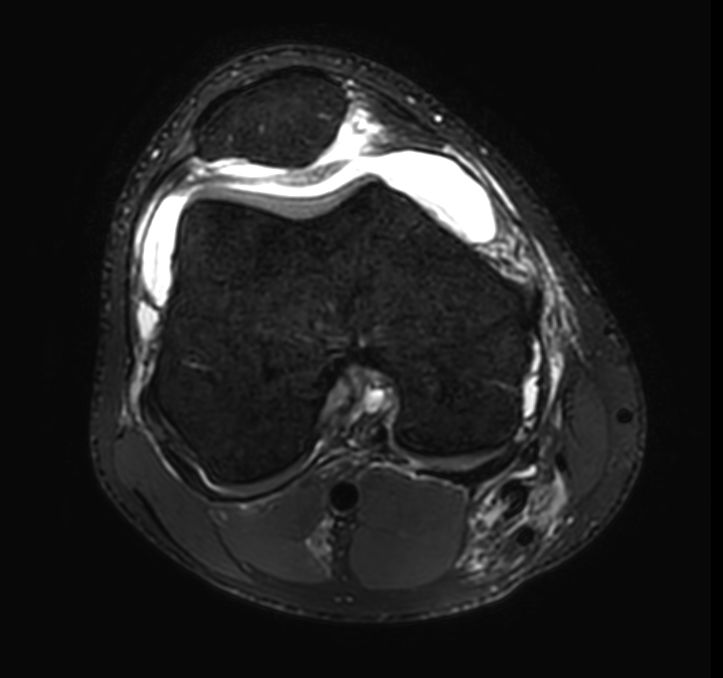

3D PDw TSE FatSat (axial reformat)